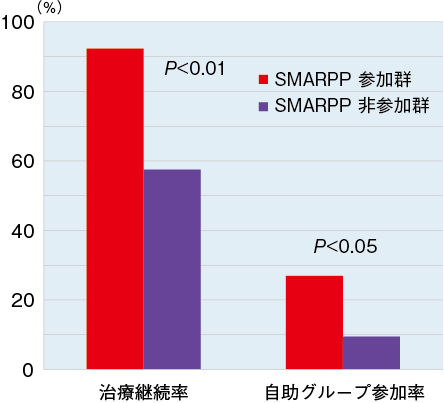

心理学ワールド 80号 罰 健康問題としての薬物依存症 薬物依存症からの回復のために医療者にできること 日本心理学会

勉強会報告 依存症治療について 薬物依存とプロセス依存 なごみ薬局